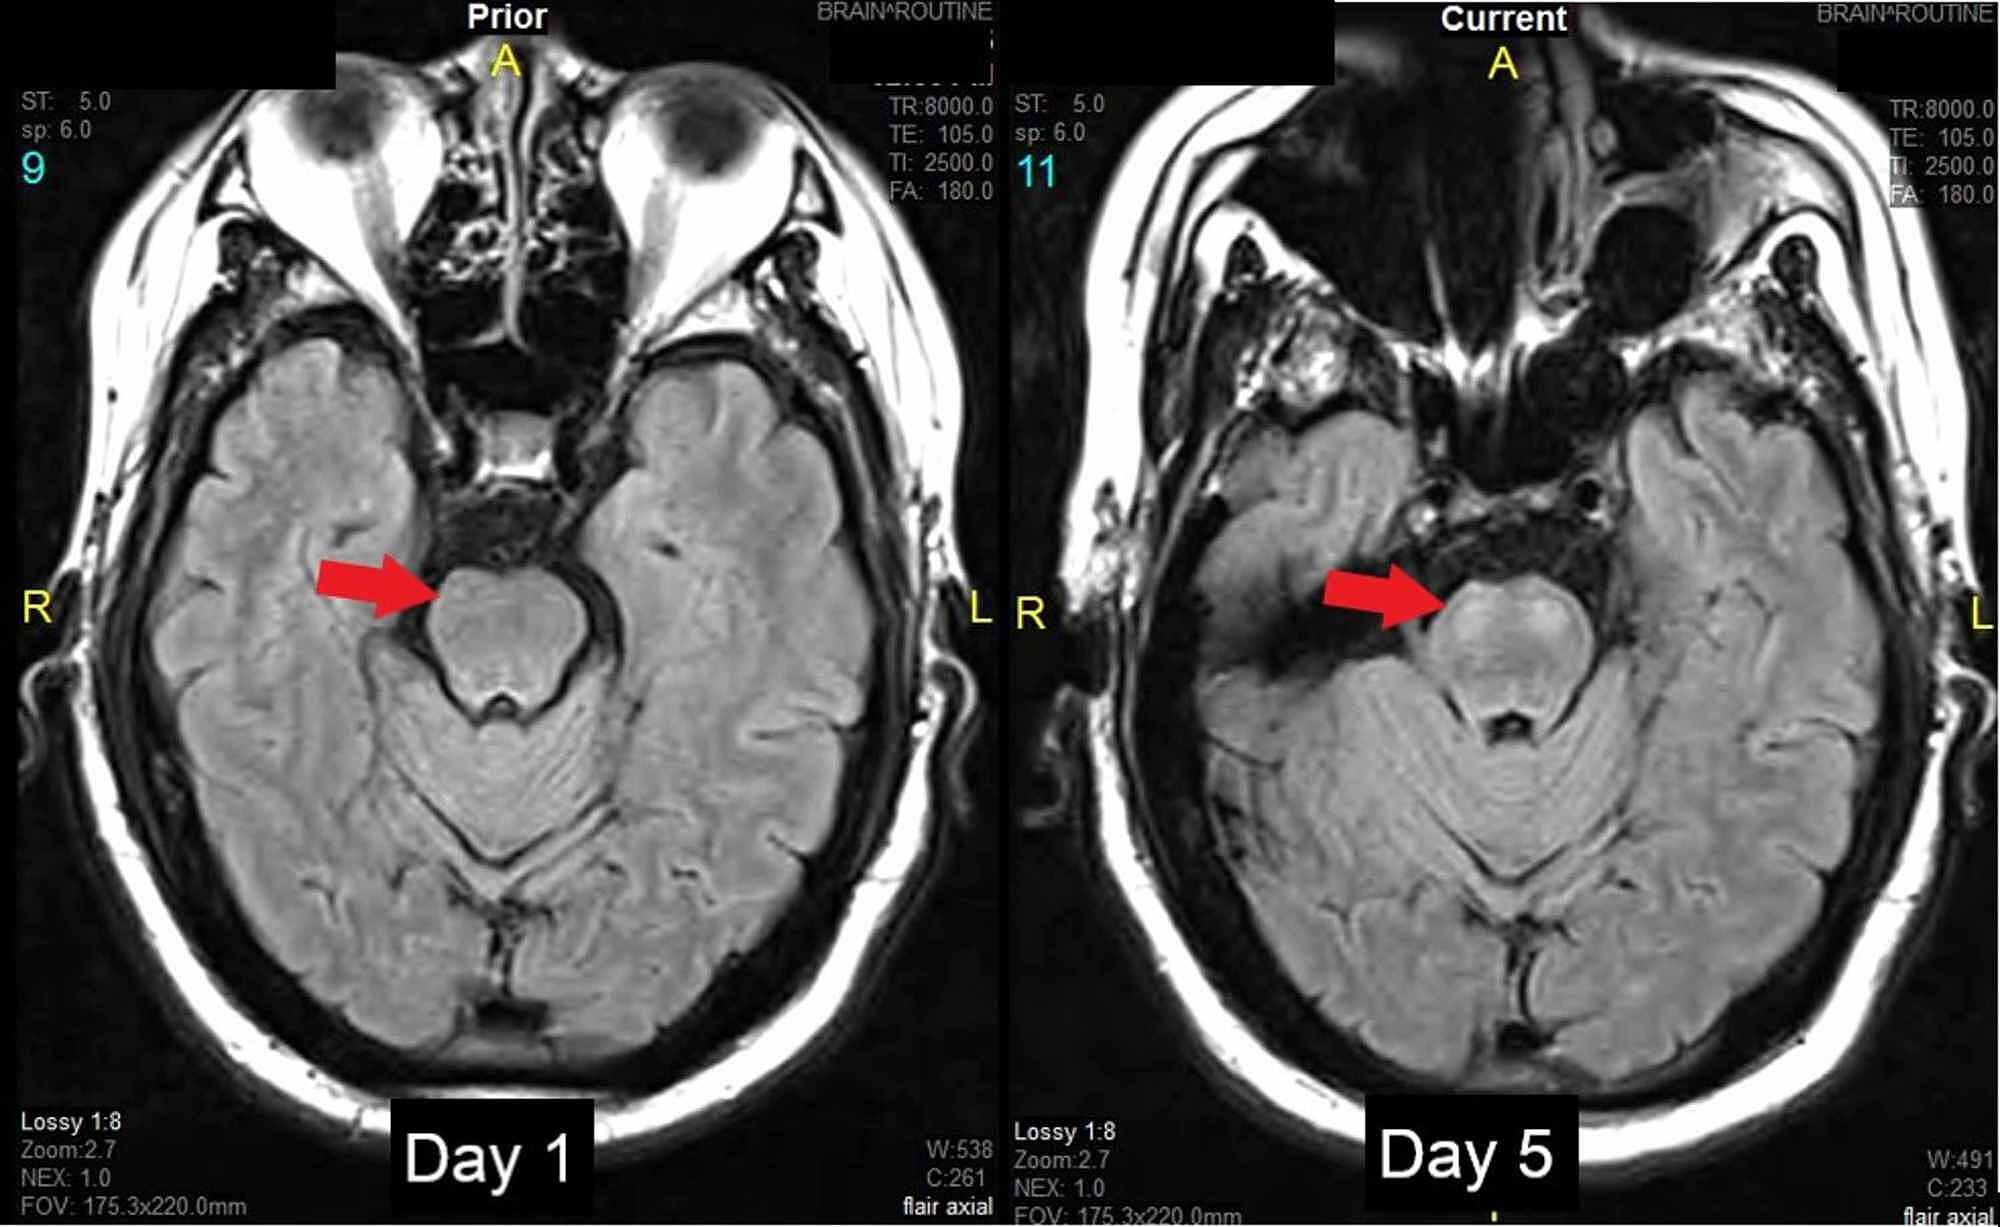

Cureus FalseNegative Initial Resonance Imaging in Acute Posterior Circulation Stroke

From www.cureus.com

Cureus FalseNegative Initial Resonance Imaging in Acute Posterior Circulation Stroke What Is A Mri Negative Stroke With the increasing use of dwi as the imaging of choice in acute stroke, dwi negative stroke must be considered in patients who. It is superior to ncct to early detection of acute ischemic. Brain mri with dwi has the most sensitivity and specificity and is the best option to diagnose acute stroke. Neuroimaging in the evaluation of acute stroke. What Is A Mri Negative Stroke.